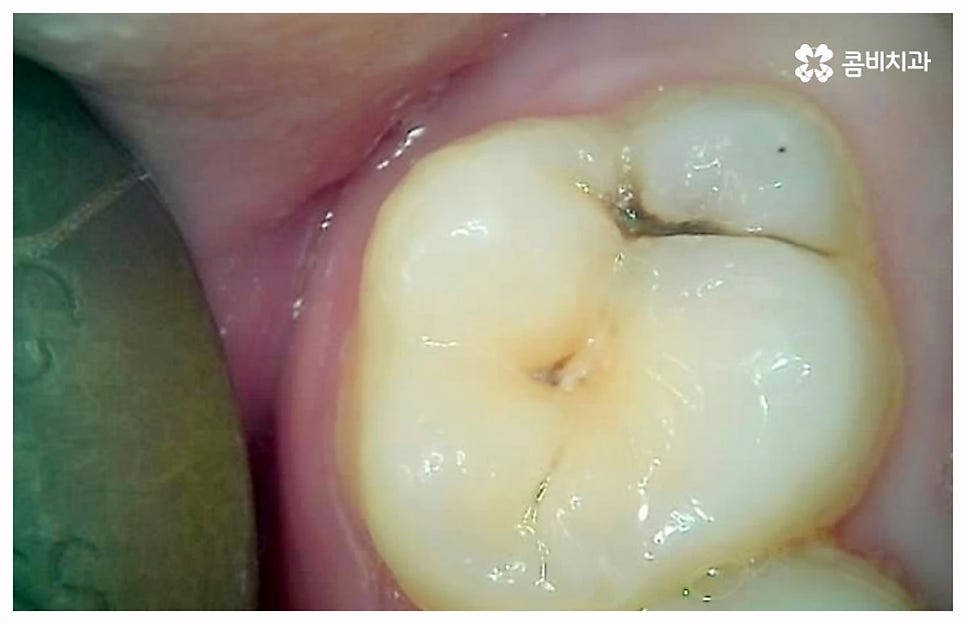

출처 아카이브 열기치통의 원인은 굉장히 다양한데 그 중 가장 대표적인 것으로는 구강 질환과 치아파절을 생각해 볼 수 있을 거예요. 충치나 잇몸병과 같이 구강 내부 상황으로 인해 발생하는 것이 구강 질환이라면 외부에서 충격을 받아 치아가 부러지거나 깨지는 것을 치아파절 이라고 할 수 있는데요. 이렇게 내적 또는 외적인 원인으로 생긴 치아 손상은 자연적으로 낫지 않으며 시간이 지날수록 빠르게 악화되기 때문에 구강 질환이 발생했거나 치아가 파절되었을 때 시기를 늦추지 말고 바로 치과에 내원하셔서 꼼꼼하게 검진을 받고 상황에 적합한 치료를 받으실 필요가 있습니다.

충치나 잇몸 질환은 보통 단계적으로 서서히 발전하기 때문에 환자분들께서 하루 아침에 극심한 통증을 느끼게 되는 경우는 많지 않지만 혹시라도 갑작스럽게 치통이 심할때 혹은 밤에 자려고 누웠는데 더욱 치통이 심할때 는 급성치수염을 의심해 볼 수 있어요. 급성치수염은 언급했던 충치나 외상성 치아 파절로 인해 치아 가장 안 쪽에 있는 치수 부분까지 세균이 침투하여 염증이 발생하는 것을 의미하는데, 이 때 감염된 혈관이 부어오르면서 단단한 치아 외벽에 둘러쌓인 치아 내부 압력이 올라가 작은 움직임에도 극심한 통증을 느끼게 되는 거예요.